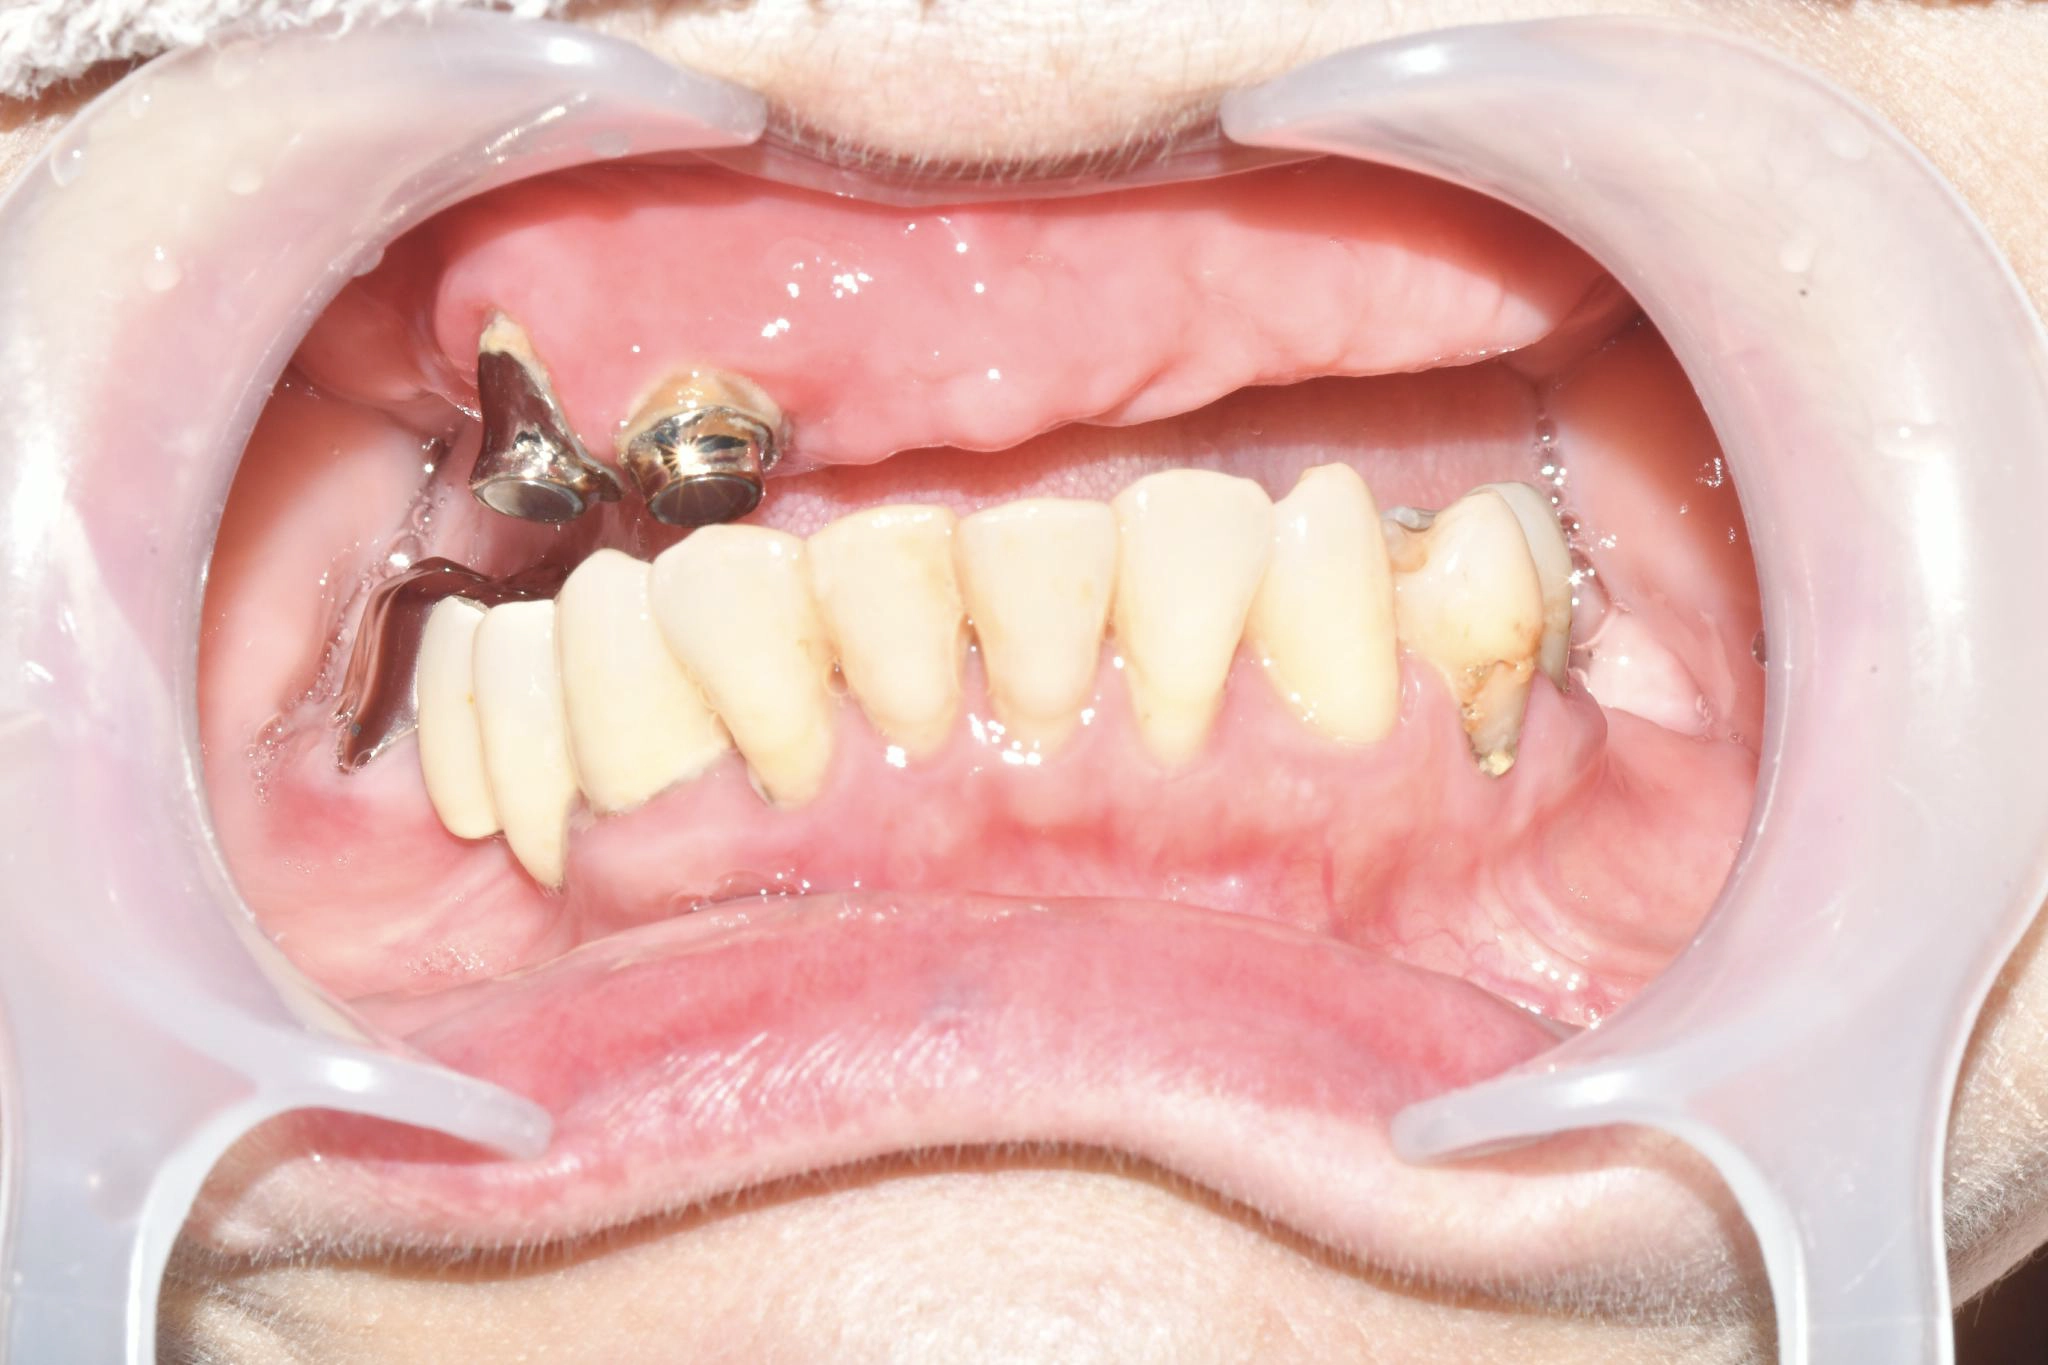

術前

磁石固定式の義歯を使用していましたが、頻繁に外れる上に痛みも伴い、機能的に限界を感じていました。特に、仕事柄「味見」をする必要があるのですが、義歯では満足に味を確かめることができず、支障が出ていました。食事の際も、食べ物が当たる度に歯茎に痛みもあり、日常生活においても深刻な悩みを抱えていました。

他院への相談もしましたが、将来的な維持管理や機能回復の確実性を考慮した結果、こちらでの治療を選びました。取り外し不要の固定式の歯になるオールオン4ザイゴマこそが、仕事と私生活の両立させるための唯一の手段だと確信し、手術を決意しました。